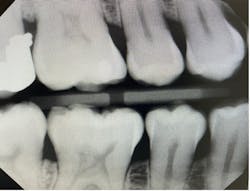

Literature suggests using the “open-door method” when contacts need to be clear and diagnostic.5 This method is achieved by moving the sensor distomesially by 15 degrees to ensure the canine is visible. This will keep the interproximal spaces open in the premolar bitewing. To avoid horizontal overlap, the central ray should be perpendicular to the arch of the teeth and directly through the interproximal spaces. With proper training and education on the concepts to mitigate overlapping, we can avoid exposing our patients to unnecessary radiation. Unfortunately, because the angle of the PID is off in Figure 1, the patient will need to be exposed to another radiograph. Proper angulation is shown in Figure 2, and proper positioning of the open-door method is shown in Figure 3.

“Horizontal angulation refers to the positioning of the PID and the direction of the central ray in a horizontal, or side to side, plane.”6 Paralleling, bisecting, and bitewings all use similar principles of horizontal angulation and will not change according to technique. The PID needs be directed toward the center of the ring using a horizontal/parallel technique. With this correct angulation, proximal spaces will be cleared, and the radiopaque enamel with either be just touching or have a distant radiolucent line of separation. This will produce a diagnostic image (figure 4) where calculus or caries lesions will not go undetected.